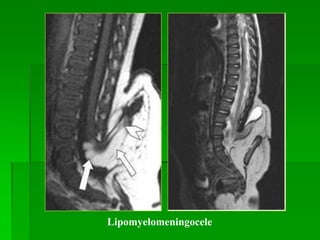

Lipomyelomeningocele

So sánh Meningocele, Myelomeningocele,

Màng tủy và

dịch não tủy

Mô thần kinh Mỡ

Meningocele + - -

Myelomeningocele + + -

Lipomyelomeningocele + + +